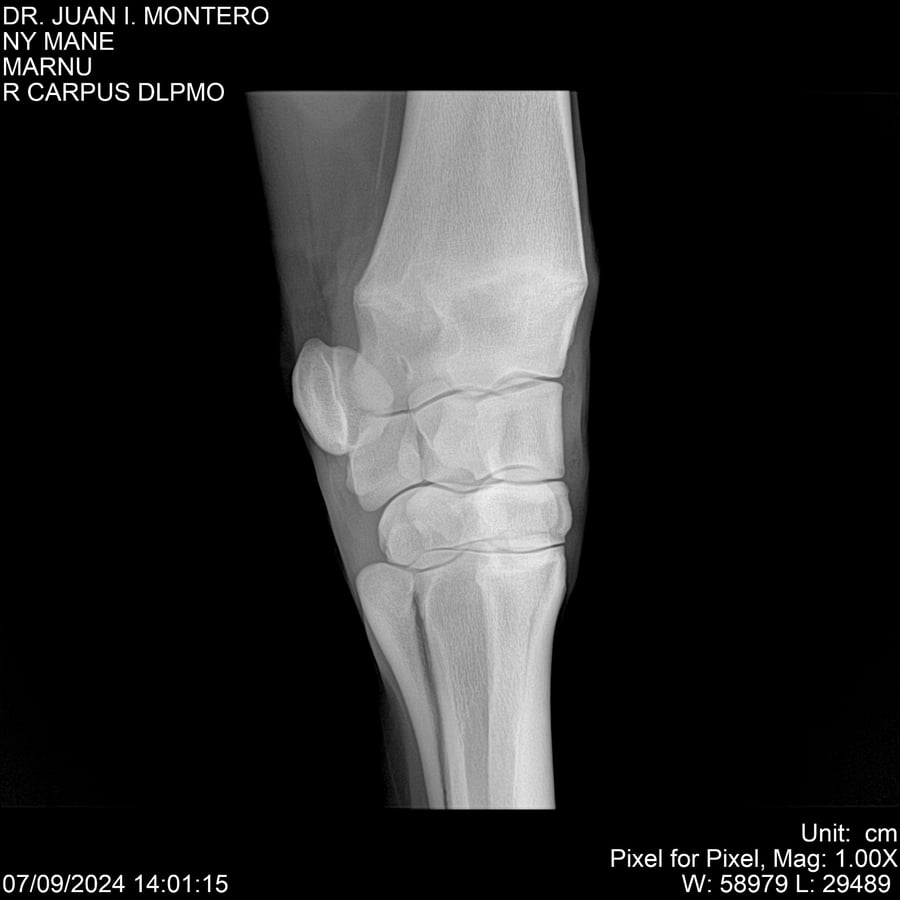

LOTE 20, NY MANE Lote Anterior Volver al remate Lote Siguiente Ficha Contacto Montevideo - Ficha del Lote Identificador: #282520 Categoría: Yeguarizos 76 Visualizaciones ClicData Contacto Empresa: Abelenda N. R., Walter Hugo Nombre*: Teléfono* : E-mail* : Mensaje Enviar Registrese gratis Este contenido Exclusivo está disponible sólo para usuarios registrados Ingresar